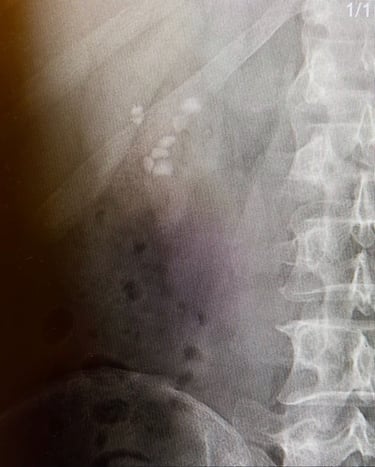

Sağ böbrekte 8 adet taş